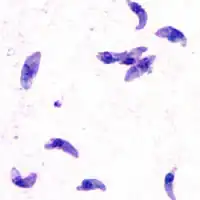

T. gondii is an apicomplexan parasite that can cause infection in humans. The parasite can live in many mammals and birds, but it carries out the sexual part of its lifecycle in cats. Feline feces from infected cats or undercooked meat from infected livestock contain T. gondii oocysts. Ingesting these could lead to toxoplasmosis, a disease which at its worst can cause encephalitis or miscarriage as the disease is passed from mother to fetus.

T. gondii and other apicomplexan parasites rely on actin-dependent gliding motility in order to gain access to the body. This form of cellular motion requires profilin, an actin filament binding protein that helps restructure the actin cytoskeleton. Without profilin, T. gondii can still grow and replicate, but it loses the ability to pass through cell layers and biological barriers in order to carry out infection. Thus profilin is a conserved, essential protein for T. gondii infection efficacy.[12]

Profilin from T. gondii is a critical parasite ligand for TLR11. It preferentially induces IL-12 production in dendritic cells that communicate with natural killer cells and cytotoxic T cells. In one study, mice bred to not express TLR11 (knock-out mice) did not mount the IL-12 response upon profilin stimulation. Dendritic cells in the knock-out mice also failed to migrate to lymph nodes, halting the initiation of the adaptive immune response.[2]

Furthermore, mice lacking the TLR11 gene are susceptible to pancreatitis, fat cell necrosis, and increased inflammatory reactants. Pancreatitis is also a pathological response in humans to T. gondii infection.[3] Wild-type mice are able to produce an immune response, marked by IL-12 and IFN-gamma production that is unseen in humans, who lack a functional TLR11 protein.